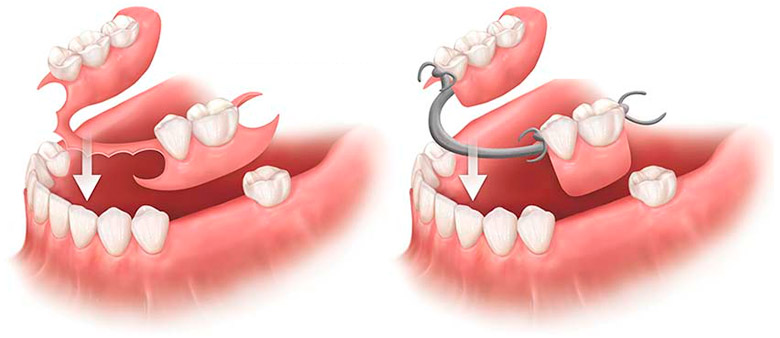

Una prótesis removible es un dispositivo dental que se puede quitar y poner para reemplazar uno o más dientes perdidos. Estas prótesis ayudan a restaurar la función masticatoria, la estética y el habla, y pueden ser parciales (para reemplazar algunos dientes) o completas (para reemplazar todos los dientes). Son una alternativa a las prótesis fijas y a menudo son una opción más económica.

- Prótesis parciales:

Se utilizan cuando el paciente conserva algunos dientes naturales y se reemplazan los faltantes. Pueden ser de diferentes materiales, como acrílico, metal o termoplástico. - Prótesis completas: